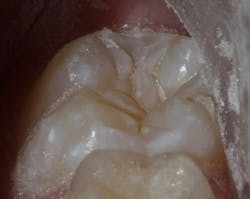

Sealant placement techniques should include complete isolation and an intermediary bonding layer (figure 1).25–29 The bonding layer and sealant curing can be one of two different methods: either placement and light-curing simultaneously in a simplified sealant technique or separately. Evidence-based studies show results favoring the individual light-curing technique in cases where conditions are dry and noncontaminated. In cases where there is saliva contamination, bond strength was the same in either simultaneous or individual light-cure placement methods.30–31